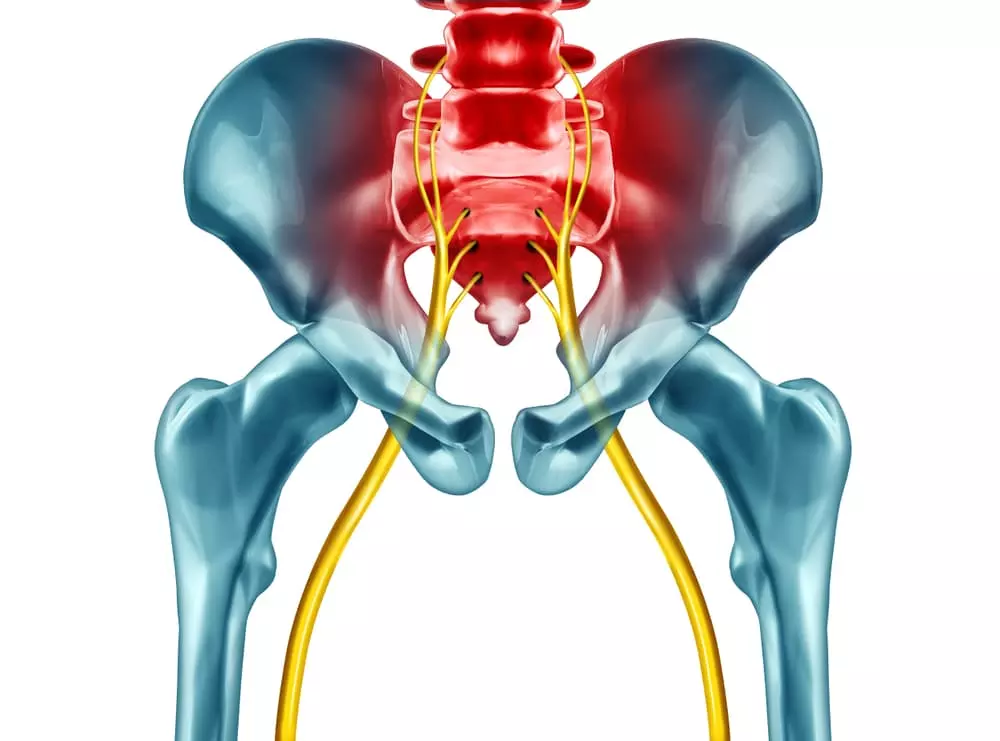

坐骨神経痛の原因

坐骨神経痛は

原因の見極めが重要。

坐骨神経痛とは、身体のどこかで坐骨神経が圧迫されることによって発生する痛みです。

しかし、その原因は単に神経が圧迫されることではなく、その背後にある要因にあります。

主な原因として、骨格の歪みが挙げられます。

この歪みがさまざまな疾患を引き起こし、結果として坐骨神経痛を誘発します。

具体的な疾患には

- 腰椎椎間板ヘルニア

- 脊柱管狭窄症

- 梨状筋症候群

などがあります。

また、妊娠や出産も坐骨神経痛の要因となることがあります。

例えば、腰椎椎間板ヘルニアでは、骨格の歪みにより椎間板が損傷し、その一部が坐骨神経を圧迫します。

脊柱管狭窄症では、骨格の歪みが長期間続くことで、脊柱管が狭くなり神経が圧迫されることが原因です。

梨状筋症候群は、骨盤のズレや股関節の問題により、梨状筋が坐骨神経を圧迫することで発生します。

このように、坐骨神経痛の原因は多岐にわたります。

それぞれの原因に応じた対策が求められるため、坐骨神経痛を単一の症状として捉えるのではなく、その背後にある原因を正確に理解することが重要です。